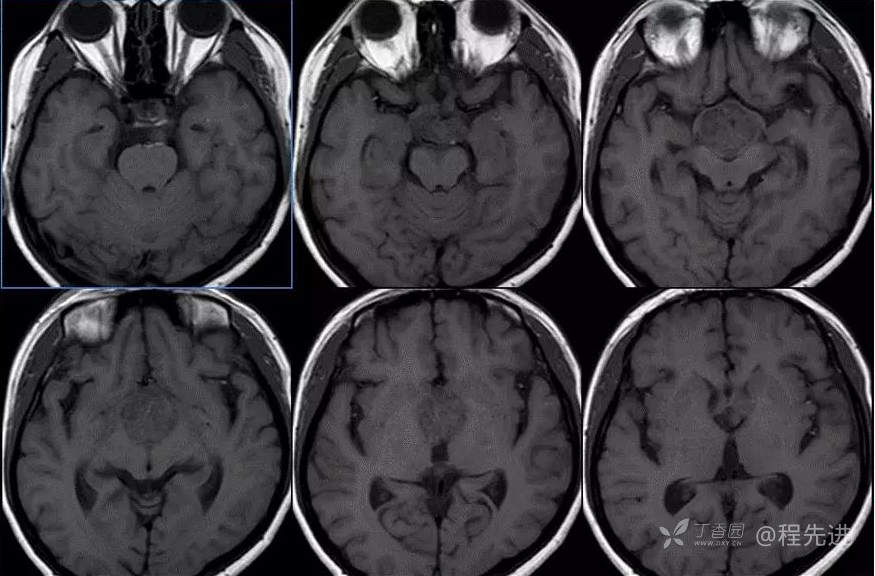

图像依次为T1横断位、T2横断位、T2FLAIR横断位、T2冠状、T1矢状、T1增强横断、矢状、冠状位